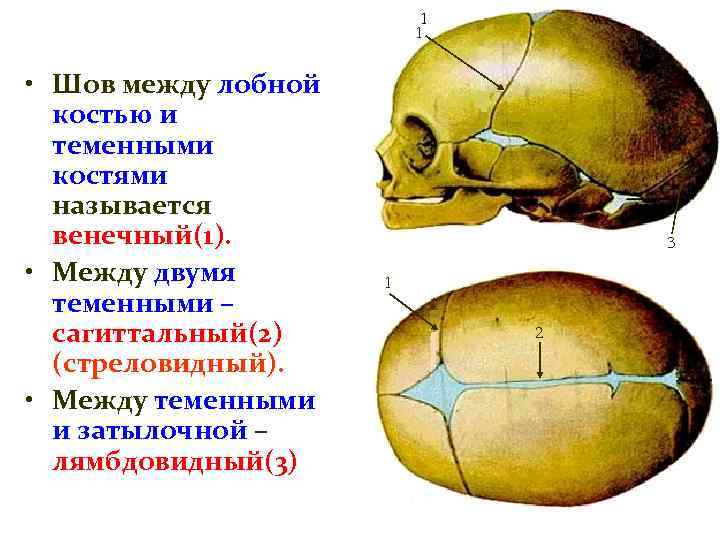

Анатомические изображения срединной сагиттальной линии черепа